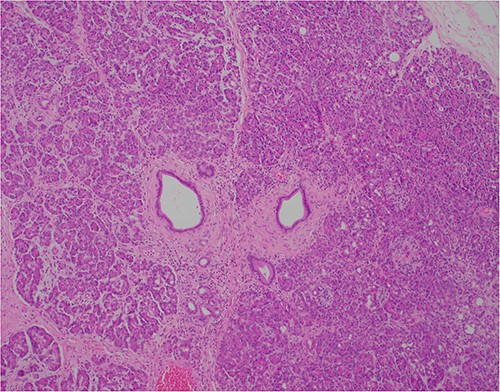

At outpatient phone clinic review 2 months post-surgery, the patient had recovered well, and his pre-operative symptoms of nausea, vomiting and pain had completely resolved. The histopathology of the gallbladder found chronic cholecystitis with cholelithiasis, in addition to a 6 mm focus of pancreatic heterotopia in the gallbladder wall. This heterotopic tissue contained acini, ducts and islet cells, classifying it as Type I pancreatic heterotopia (Figs 1–3).

×10 objective lens; showing central duct with surrounding pancreatic acini and islets, with preserved architecture.